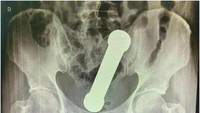

Eksperimen seksual yang aneh mengakibatkan seorang remaja laki-laki berusia 12 tahun menjalani operasi setelah dia memasukkan seluruh termometer ke dalam penisnya. Akibatnya, termometer tersebut tersangkut hingga ke dalam kandung kemihnya. (Foto: Asian Journal of Surgery)